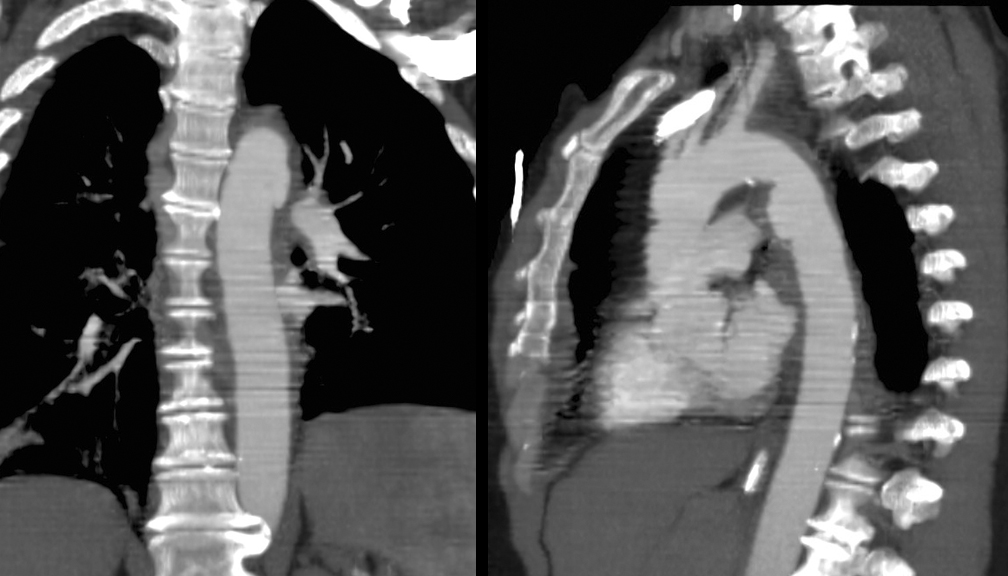

Blunt Chest Trauma

Tr Aortic Injury

Case 9d